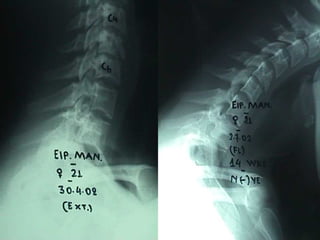

Injuries of tthhee uuppppeerr cceerrvviiccaall ssppiinnee

Μετεγχειρητικές ακτινογραφίες – 18mts